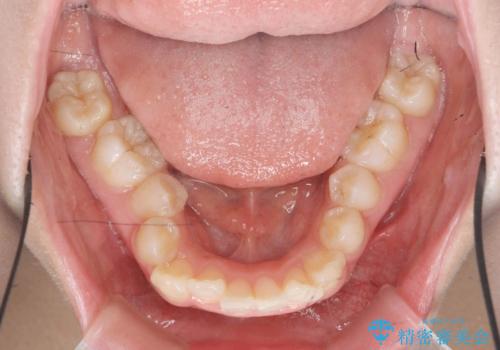

サクソフォン(アルト)の演奏で崩れてしまった歯並び、マウスピース矯正治療

- 高校時代の吹奏楽の部活でサクソフォン(アルト)を担当、「一生懸命練習をしすぎて気づいたら歯並びが悪くなっていた。矯正治療を受けたい!。」

とマウスピース矯正を希望され来院されました。

口腔内の清掃状態の良さに加えて、マウスピースを毎日きっちりと装着し、しっかりと使用していただけたことからワイヤー矯正は行わずにきれいに歯並びを治すことができました。

途中顎位が変わり、マイクロインプラントを併用した上顎臼歯の遠心移動が必要となったため治療が長期化しました。